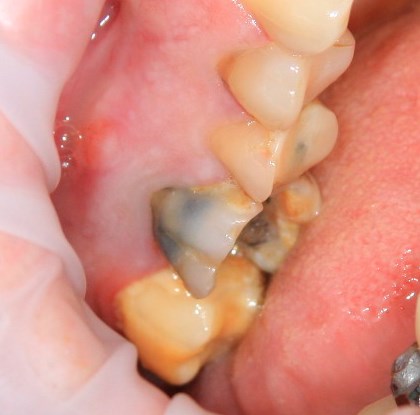

Немедленная имплантация — оптимальное решение в любой клинической ситуации